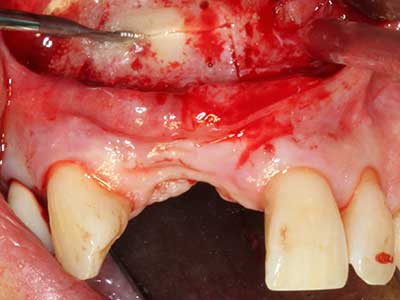

Indication: Preparation near nerves

As noted above, indications for piezo surgery can also be found in the field of conservative dental surgery. Special working tips simplify the exposure of root tips and make it easier to protect nerves and sinus mucous membranes, particularly in the lower premolar and upper posterior tooth regions. Angled diamond tips are used to precisely prepare the resection cavity for the retrograde root filler material for unsealed apical obturation. The ultrasonic technology means the tips can be very slender, which improves the view and the size of the access cavity. As a result, the application of ultrasonic surgery for this indication is one of the standard procedures for apical resection (Del Fabbro, Tsesis et al. 2010, Scarano, Artese et al. 2012).

Indication: Apical resection

When surgical procedures are performed on bone in the immediate vicinity of sensitive structures such as blood vessels or nerves, rotary instruments pose a significant risk of iatrogenic injury. Piezoelectric devices can be helpful for preparation of bone covers and removal of hard tissue close to nerves, particularly for exposure of nerves after iatrogenic injury but also during nerve lateralization for resective and reconstructive procedures or implant placement (Fig. 17-20). Light contact between the piezotip and the nerve does not generally result in damage but proceeding incautiously with saw-like motions or attachments where a residual bone substrate remains may cause temporary or even permanent nerve damage. However, the risk of damage is considered to be substantially lower than when using saws or milling instruments (Pereira, Gealh et al. 2014).